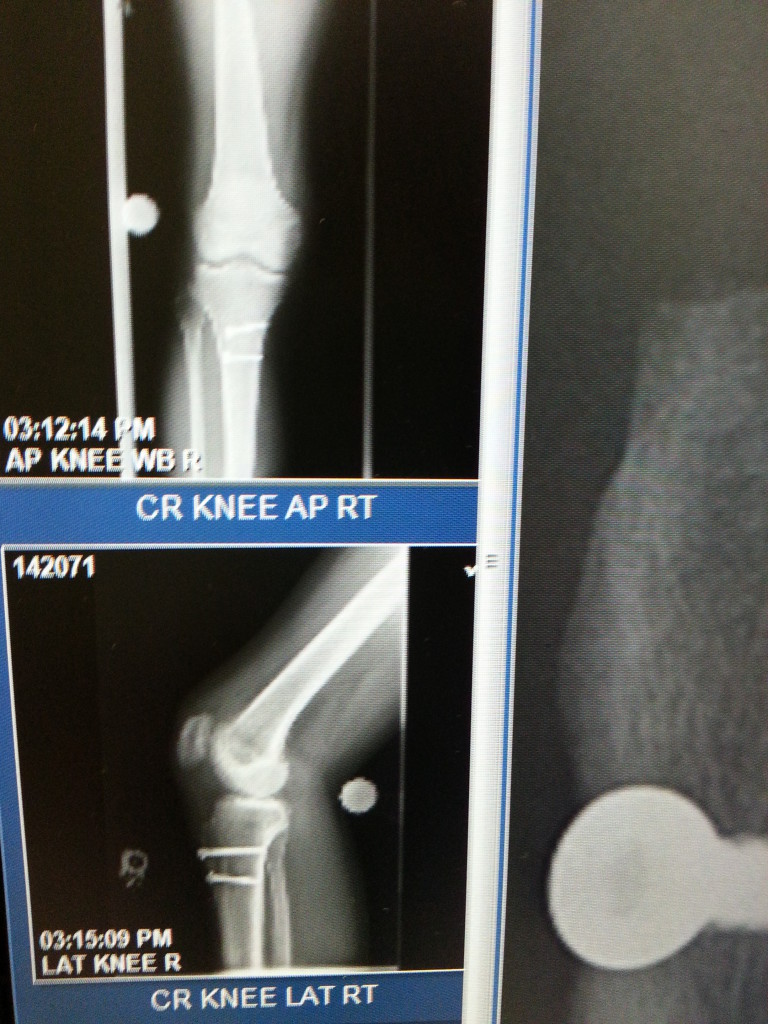

I'm a runner for over 20 years and after I ran the 2011 NYC Half Marathon, I started feeling some discomfort in my right knee, but I did not put too much attention. I went to see an orthopedic MD in Astoria and after an MRI and x-rays, he told me that my days as a runner were over, and that was one of the worst feelings that I ever experienced in my life. To know that running was over for me, I got depressed. After a few months I decided to go for a second opinion and I found Dr. Howard Rose at HSS. He ordered a new MRI. He started a series of cortisone injections that helped with the pain, but still I was not able to run. So in a follow up visit he told me that I was a perfect candidate for Dr. Beth Shubin Stein. He referred me to her and since the first visit I knew that she was the one that could help me. Dr. Shubin Stein and her great team were really honest and straight forward with me and she proposed and explained a procedure that can put me "back in the game." I agreed to do the surgery called Tibial Tubercle Transfer with Denovo implant, which was performed in 12/2012. After a year of the surgery I was running again and after almost 2 years, I ran the 2014 TCS NYC Marathon. I can't found have enough words to express how thankful and blessed I am for had a great surgeon such as Dr. Shubin Stein working on my knee. She is my superhero, my Wonder Woman and I'll be grateful for the rest of my life for to give me back the chance of enjoying  again the passion of running. Thank You HSS!